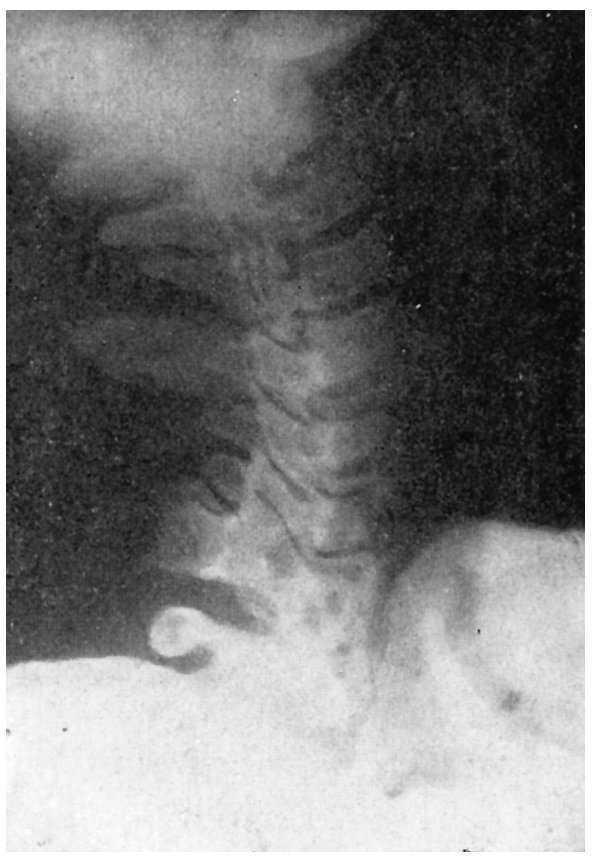

Figura 6 A.Caso núm. 1. E. A. G. Discosis 5-6a C.

Figura 6 B.Caso núm. 1. E. A. G. Radiografía en extensión. Anquilosis perfecta.

Figura 6 C.Caso núm. 1. E. A. G. Radiografía en flexión. Anquilosis perfecta.